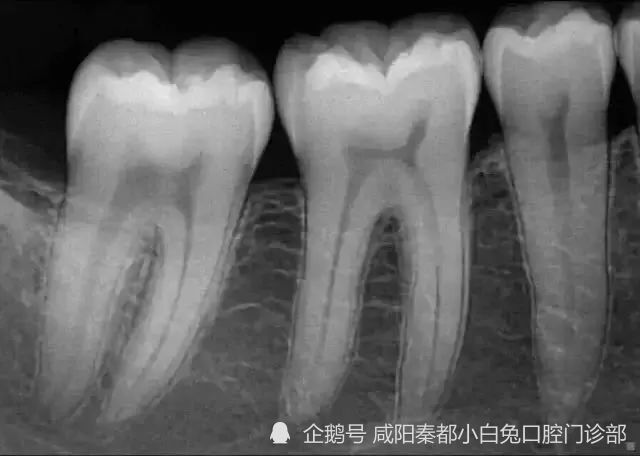

小牙片的正确拍摄方法,小牙片拍摄技巧图解

小牙片拍摄技巧图解

牙片拍摄技巧图解

小牙片